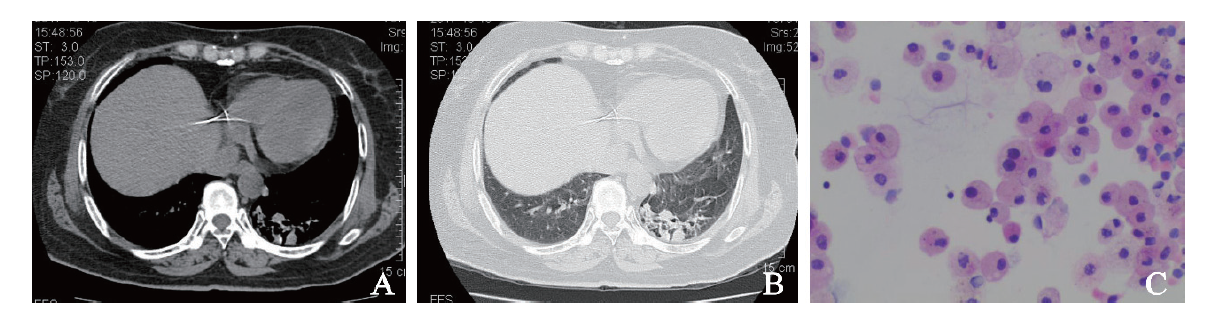

例2 患者男,68岁。因左肺腺癌1年返院复查于2017年7月18日收入我科。1年前患者因后背痛10月余,加重伴胸痛20 d在我科经胸部CT、肿瘤标志物、胸腔积液病理及免疫组化等检查确诊为左肺腺癌,于2016年8至12月行多西他赛120 mg、洛铂50 mg方案化学治疗6个疗程,过程顺利。既往吸烟30年,每日1包,戒烟2年,余无特殊。入院体格检查:体温36.7 ℃,脉搏100次/分,呼吸20次/分,血压144/93 mm Hg。双肺呼吸粗,未闻及干、湿性啰音。血常规示血红蛋白119 g/L,白细胞7.98×109/L,血小板 155×109/L。癌胚抗原21.0 μg/L,神经元特异性烯醇化酶、细胞角蛋白19片段、鳞状细胞癌相关抗原测定等正常。复查胸部螺旋CT平扫+增强扫描示左侧肺癌较前增大,左肺、左侧胸膜多发转移瘤较前稍增大(图2A、B)。遂完善BAL检查。7月25日BAL的HE涂片及液基细胞学检查示较多泡沫样细胞及少量上皮细胞,未见确切癌细胞(图2C)。予培美曲塞800 mg、顺铂120 mg化学治疗,过程顺利,予出院。随访至2018年8月5日,患者再次化学治疗,过程顺利。

图2 例2肺腺癌患者的胸部CT及BAL涂片结果

A:胸部CT纵隔窗;B:胸部CT肺窗;C:BAL涂片(HE染色,×400)